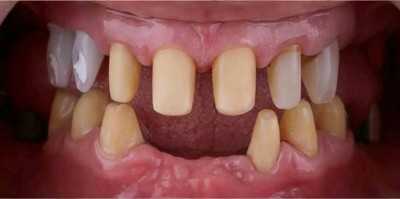

Озеров Петр специализируется на хирургической стоматологии и импланталогии, блестящий специалист по лечению и удалению кисты. Является постоянным участником курсов, семинаров и международных конгрессов по имплантологии и ортопедии. Петр Владимирович проводит протезирование как классическими методиками керамикой и металлокерамикой, так и протезами на драгсплавах (диоксид циркония, алюминий), и эстетическое протезирование винирами и люминирами. Кроме протезирования и имплантации, доктор выполняет и хирургическую подготовку к ним: операции по костной пластике с применением искусственной кости и аутокости (собственной кости пациента).